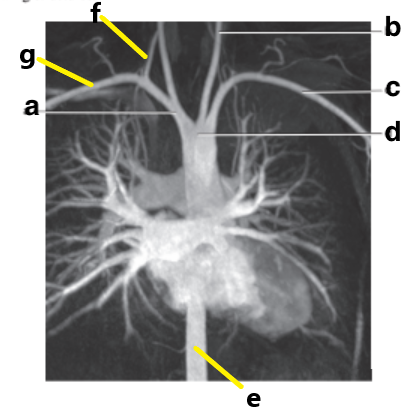

Subclavian artery

A

Vertebral artery

f

Aortic arch

Abdominal aorta

Brachiocephalic trunk

Which letter is the Right vertebral artery?

Ascending aorta

Descending aorta

Carotid bifurcation

Common carotid artery

Basilar artery